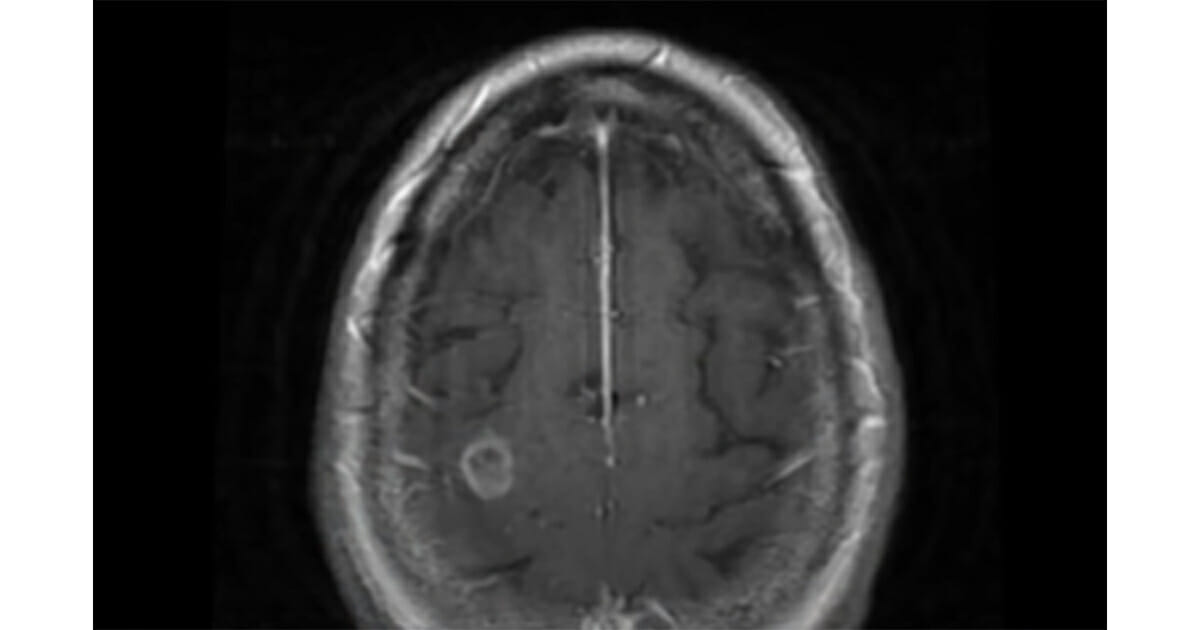

At the time of her seizure, the woman’s medical team were left stumped. They suspected a brain tumor initially, but during surgery they realized they were removing only dead brain tissue.

Doctor Charles Cobbs, part of the team at the Swedish Medical Center, said: “The pathologist was able to look at it under the microscope and see the characteristic … actually the amoeba in the tissue.”